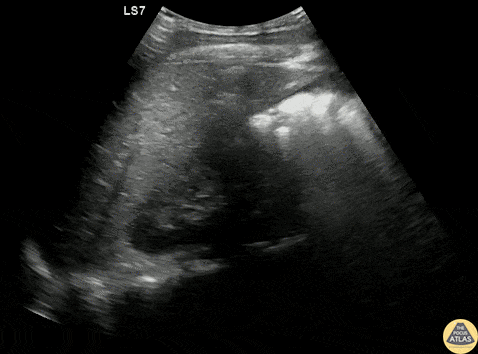

Trauma - RUQ +FAST

A teenage male patient presented to the ED after a helmeted mountain bike crash, and due to mechanism, underwent a bedside FAST exam, which was positive in the RUQ as well as suprapubic views. CT demonstrated a grade 4 spleen laceration as well as multiple buckle rib fractures, and he was admitted for observation. Dr. Gabe Siegel, PGY-2 and Dr. Michael Kidon, PGY-4 Denver Health Residency in Emergency Medicine